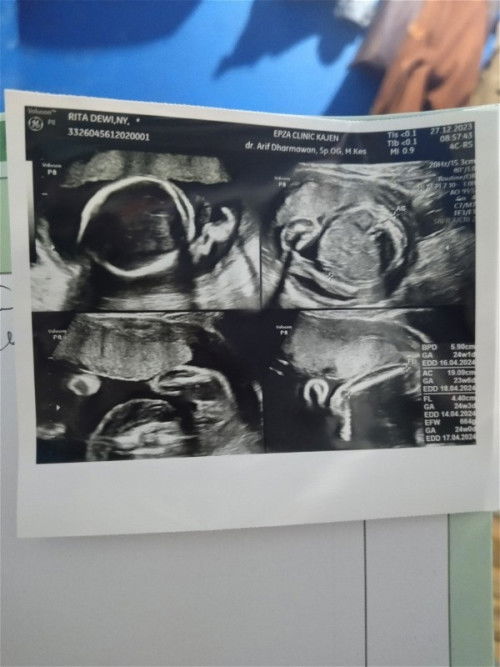

hasil usg 23 week, ada yang udah usg juga ga?

jd aku habis usg bun, katanya kemungkinan perempuan, cuma blm pasti karena posisi bayinya. disuruh balik lagi buat memastikan terus sekalian yang 4d biar jelas. aku tanya air ketuban cukup ga dok? posisi plasenta gmn dok? posisi janin gmn dok? biar bayar usg mahal ga cuma2 krn dokter disini klo kita ga tanya ngejelasinnya ga terlalu detail. 😆 kira2 beneran perempuan ga ya bun, klo aku sih sedikasihnya krn anak pertama jg yang penting sehat tanpa kekurangan🤭 #firstmom